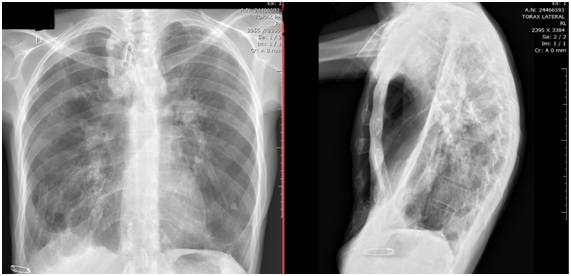

A 30-year-old male patient was hospitalized in a pneumological intensive care unit, with dyspnea, fever, desaturation, requiring nasotracheal intubation and the use of mechanical ventilation under controlled pressure. History of various procedures in the larynx since 13 years of age, with medical diagnosis of tracheal amyloidosis. In a 10-day period, 2 extubation attempts were performed, but the patient did not tolerate weaning protocols. Initially referred for tracheostomy. During withdrawal of the nasotracheal tube, the nasoenteric tube was removed. In Figure 1 we present RX of Thorax in which the deviation can be observed in the cannula of the patient's tracheostomy.

Figure 1 Rx of Torax.